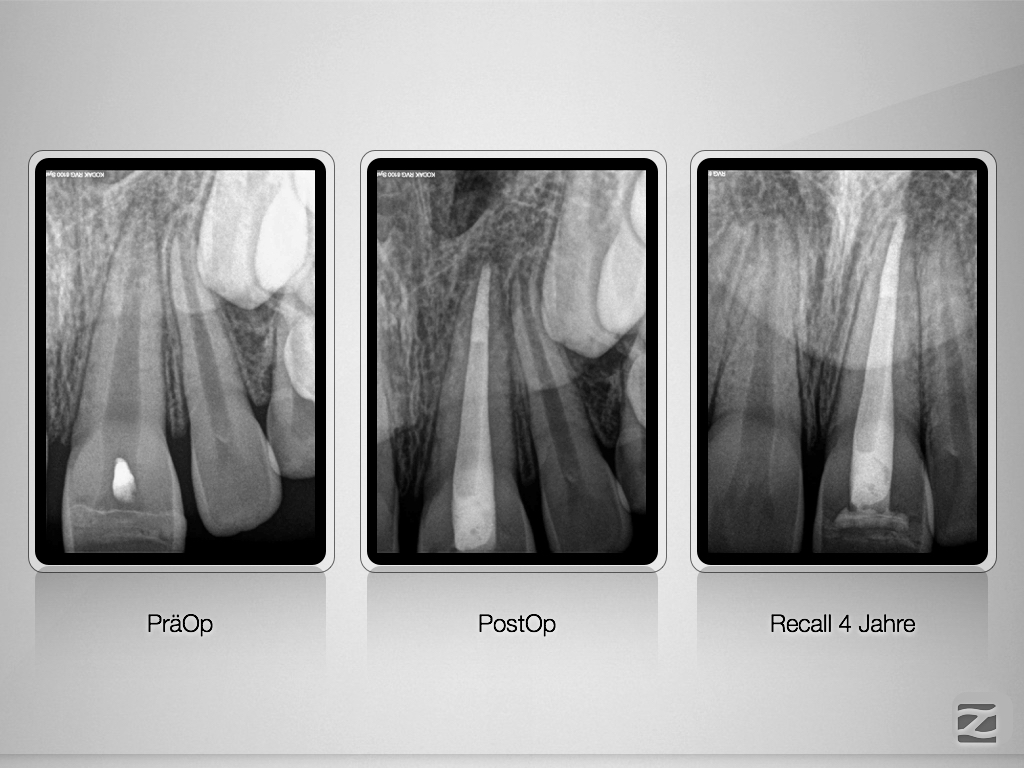

21D Recall.001

Revitalisierung oder MTA-Plug?